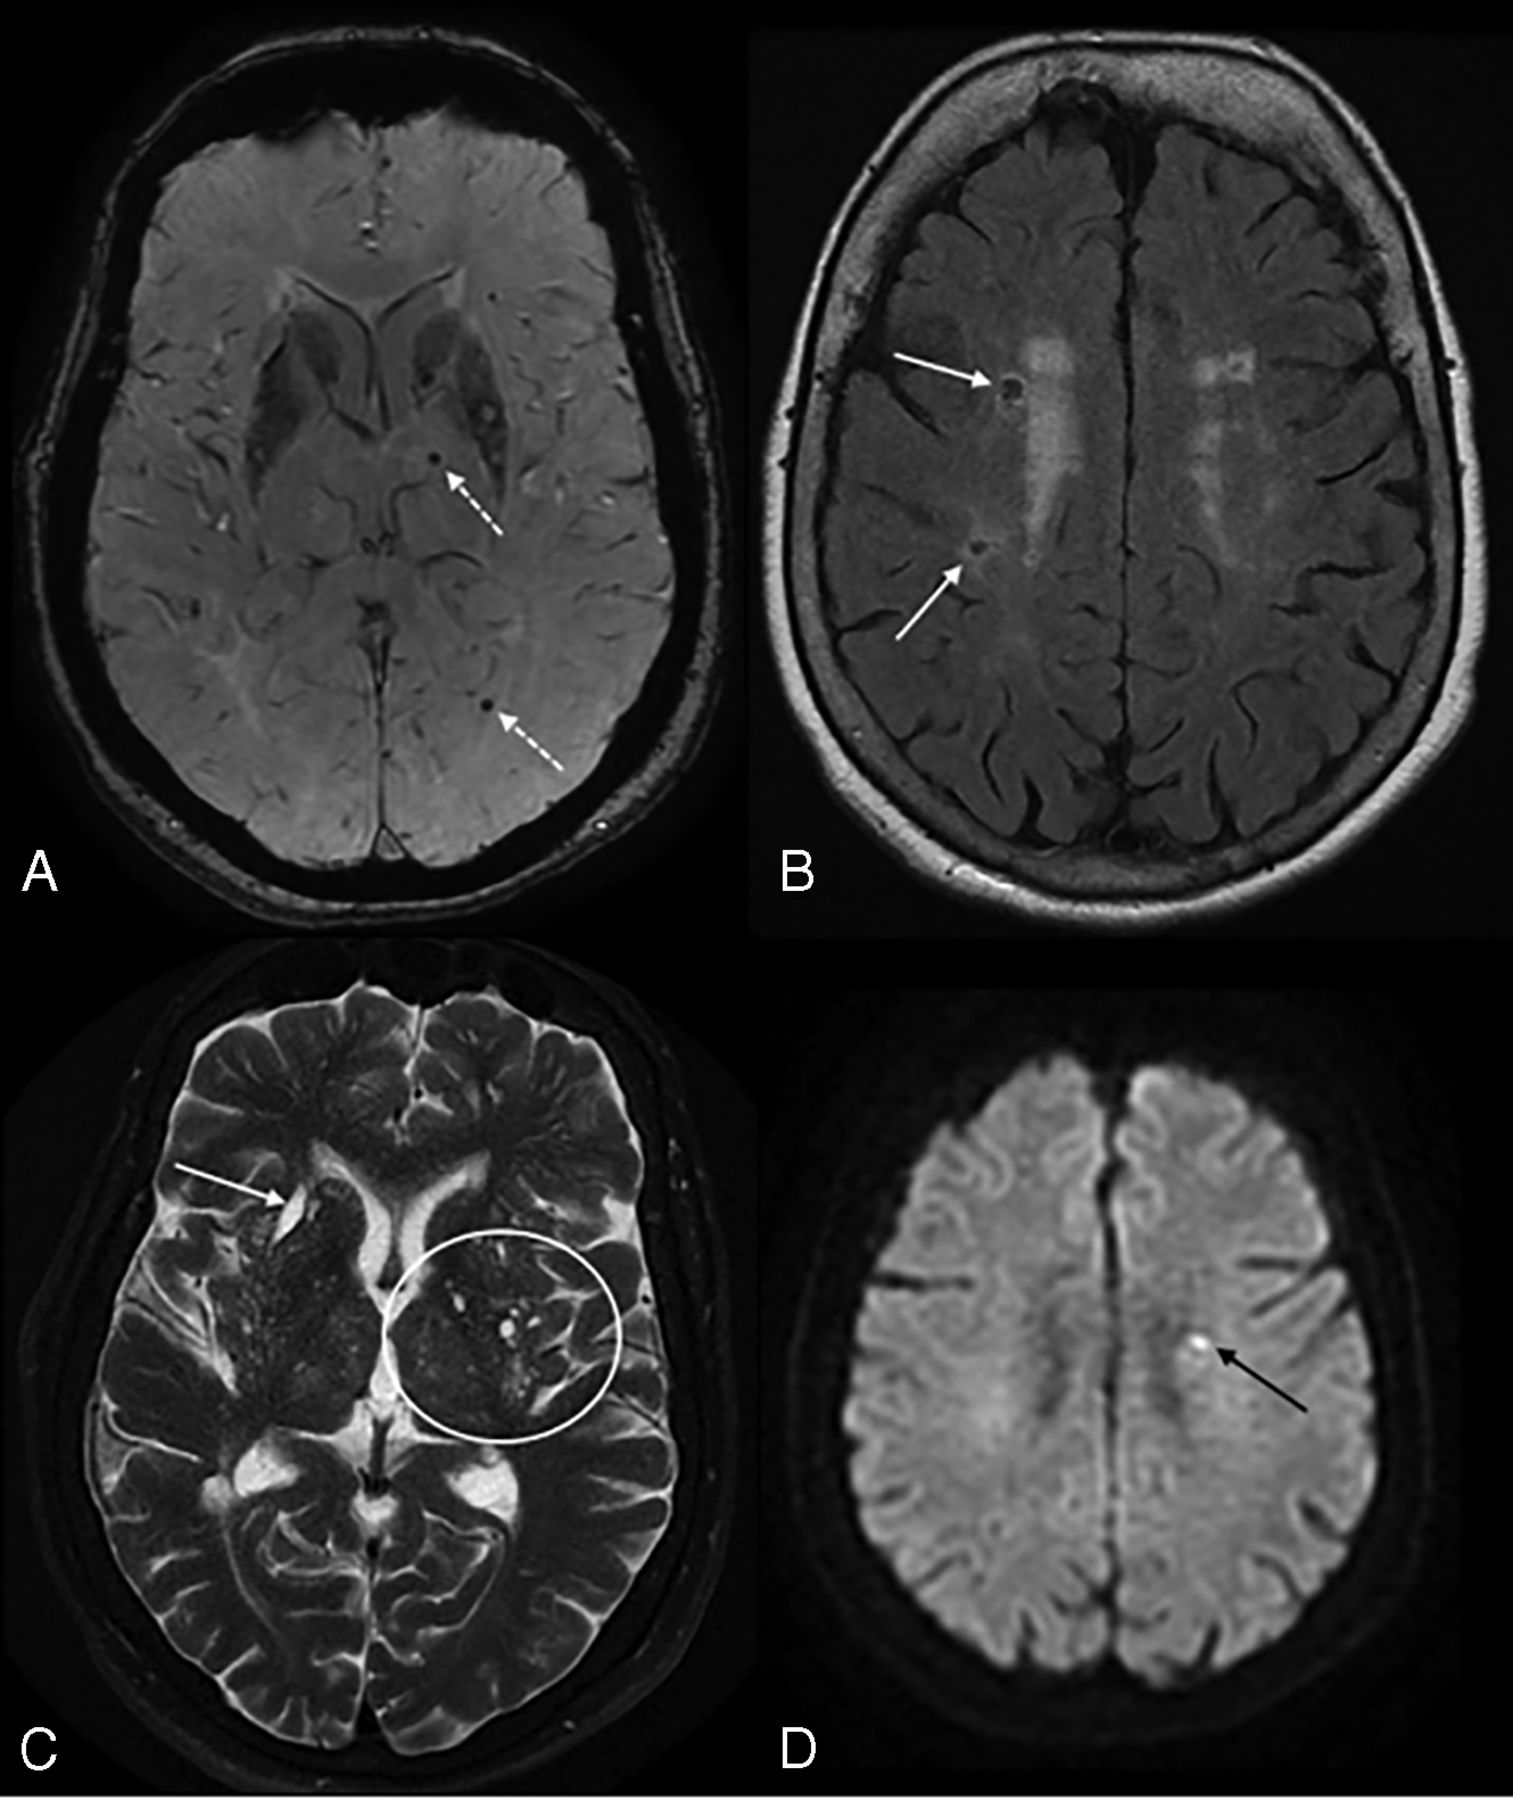

Although the neuroimaging markers have typical characteristics, in practice, it is difficult to distinguish lacunes, PVS, and WMH of presumed vascular origin because they are often closely related. A few studies have suggested combining these MR imaging markers and using a more comprehensive approach to assess total SVD burden.33,40 Total SVD score is a simple and pragmatic way of assessing overall brain health and has been shown to be a prognostic indicator of cognitive decline and recurrent stroke (Fig 5). The total burden of lesions in specific anatomic locations can also be used for lesion-symptom associations and has been shown to be associated with cognitive impairment and gait and mood disorders.5,40,41 For instance, a total SVD score in CAA was proposed by Charidimou et al33 and can potentially provide a more practical framework to better evaluate the effect of CAA-related brain damage on clinical outcomes. A similar total MR imaging SVD burden approach was proposed in HA by Klarenbeek et al.42 The imaging rating points of total SVD burden are outlined in Table 2.

High SVD burden in a 55-year-old man with a history of arterial hypertension. Note multiple microbleeds in the left thalamus and occipital lobe (dotted arrows) on SWI (A), remote lacunar infarcts in the right centrum semiovale (white arrows, B), and WMH Fazekas 2 on FLAIR (B). More than 20 dilated perivascular spaces are seen on axial T2WI (circle, C) and remote lacunar infarct in right lentiform nucleus (white arrow, C). The total SVD score is 4. The patient developed an acute lacunar infarct (black arrow) on DWI (D) 10 months later.